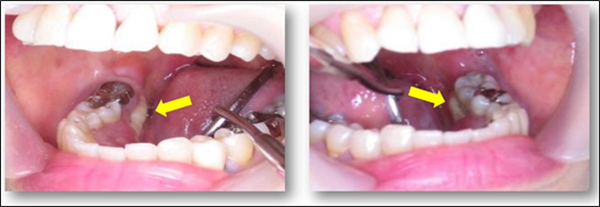

Osteonecrosis or Avascular Necrosis (AVN) of the jaw is diagnosed by clinical evaluation. The condition is confirmed when the exposed necrotic bone is present in the maxilla or mandible for at least 8-weeks.

(Image adapted from https://www.sciencedirect.com/science/article/pii/S1882761618300127))Fig.2. Clinical Photos of Osteonecrosis or Avascular Necrosis of the Jaw